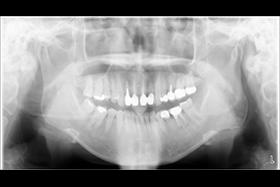

經X 光片發現牙齒底部病變 評估建議立即拔牙且立即植牙。